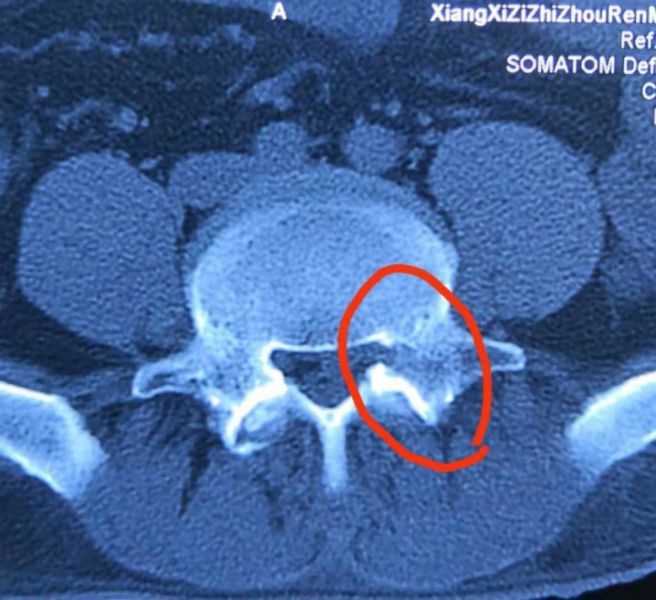

术后打磨的椎弓根骨道

术后椎弓根被打磨一半